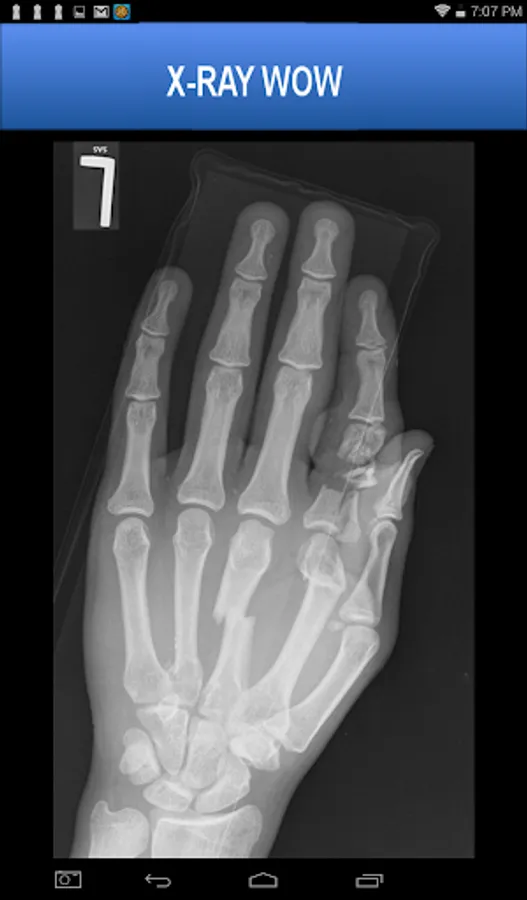

A collection of authentic x-ray images of 20 patients who have experienced serious trauma or unusual surgical procedures.

More than 55 x-ray images are included, many pointing out pathology using arrows and lines. The images may be pinch-zoomed.